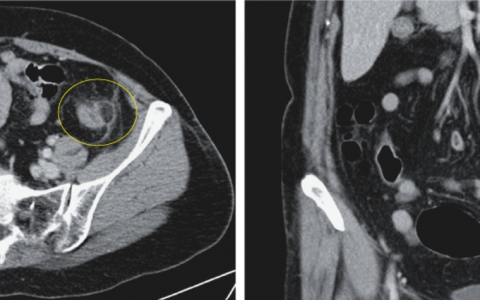

(E) In the ureter over the iliac vessels髂血管上方的输尿管